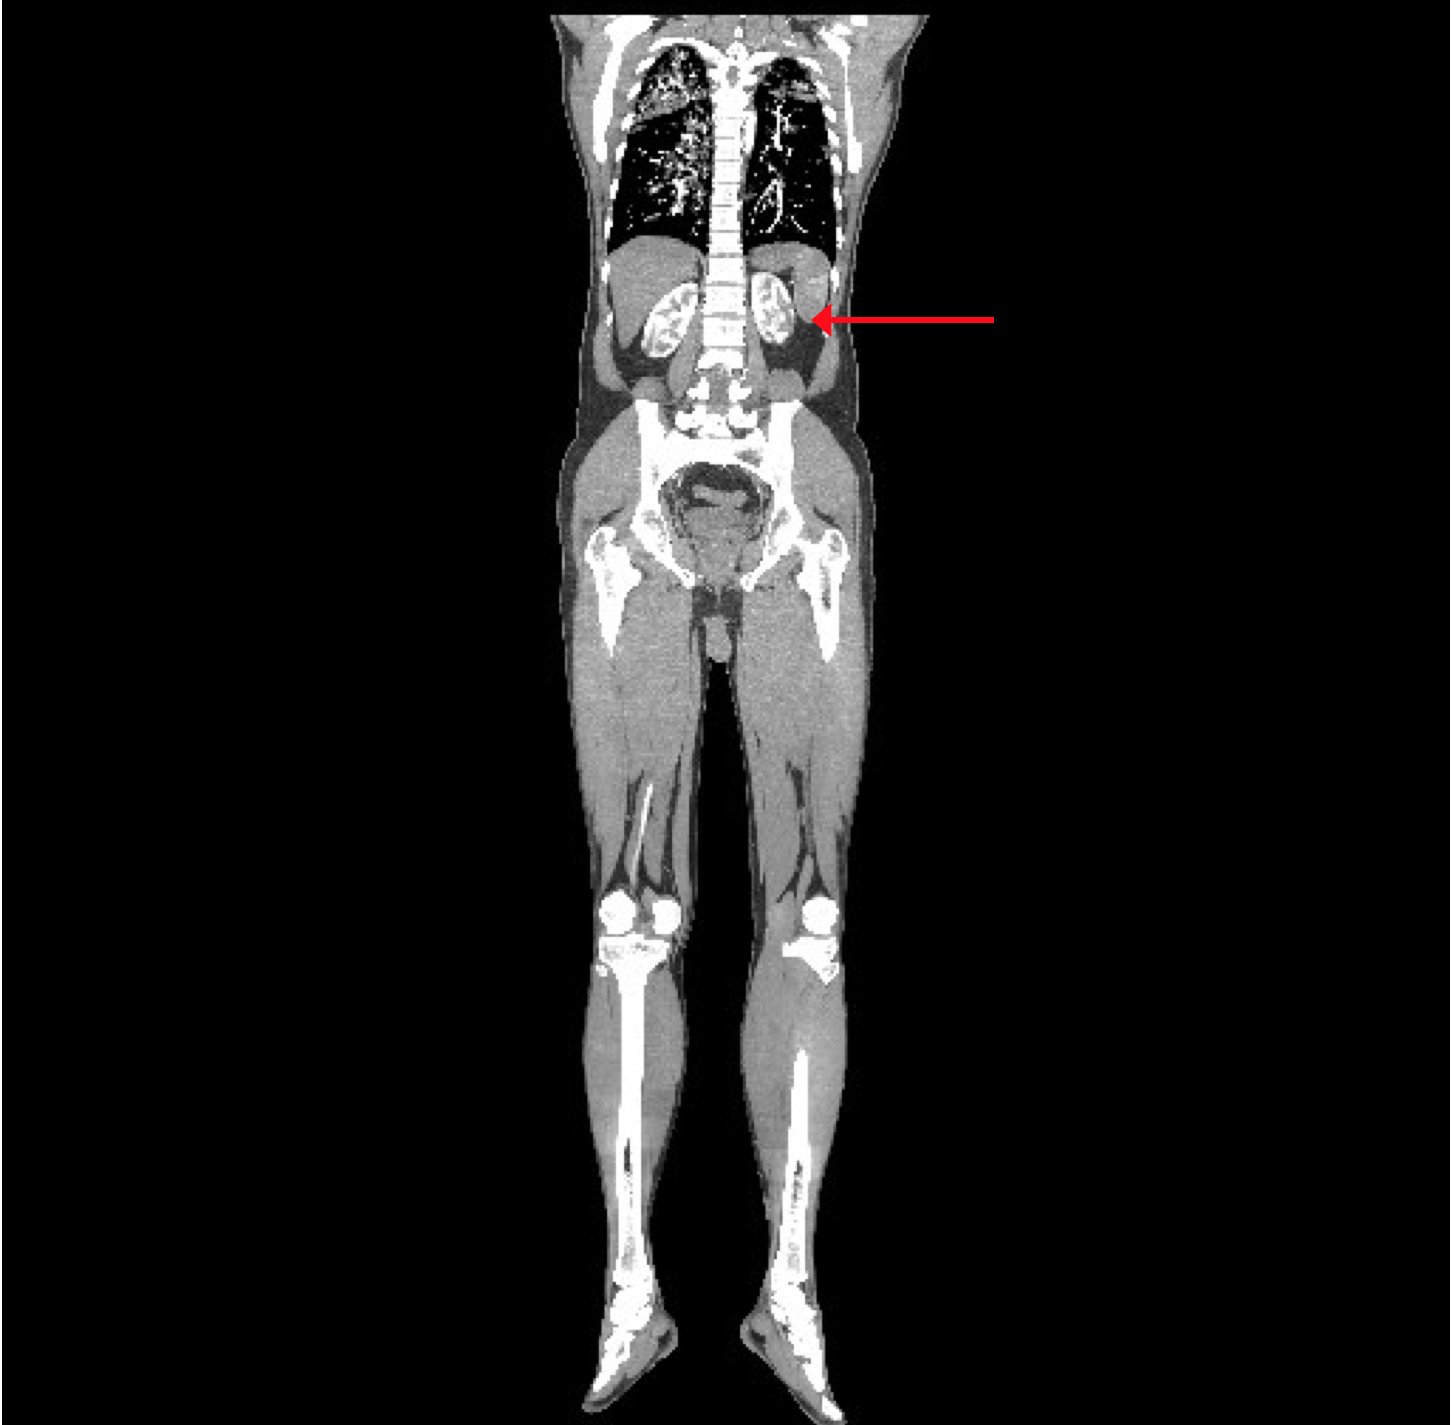

The CT angiogram and CT chest aortogram revealed a hypodense filling defect in the aorta below the level of the renal arteries causing partial occlusion of the aorta (Figure 2). There was complete occlusion of the left common iliac artery just after bifurcation of aorta extending up to the common femoral artery (Figure 3). There was good contrast uptake in right common iliac artery, femoral artery, superficial femoral artery up to the popliteal artery then the abrupt cut off of right popliteal artery present with no contrast filling seen in the distal arteries (Figure 4 and 5). Additionally, multiple bilateral wedge shaped infarcts seen in both the kidneys and the spleen (Figures 6). Chest x-ray was normal.

Figure 3: 3-Dimentional Angiogram showing a complete obstruction of the left iliac artery.

Figure 4: 3-Dimentional Arteriogram showing complete obstruction of the right popliteal artery.

Figure 5: CT Aortogram revealing multiple infarcts in the both kidneys in coronal section.